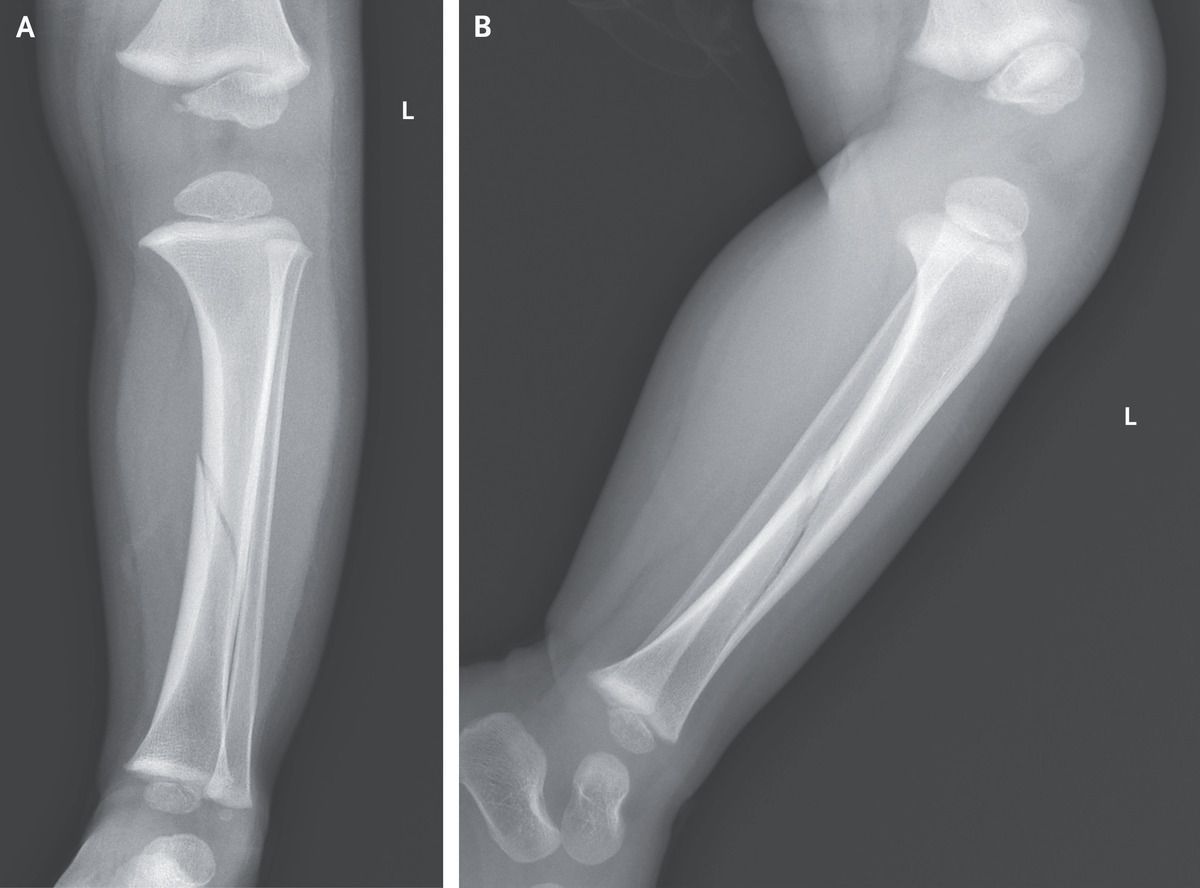

A previously healthy 20-month-old boy was brought to the emergency department with a 2-hour history of pain and swelling in the left lower leg. The pain had started immediately after he had twisted his leg and fallen to the ground when pushed by his sibling. On physical examination, the child was crying and unable to bear weight on the left leg. The left lower leg was tender to palpation and painful with passive dorsiflexion of the ankle. Radiographs of the left lower leg showed a minimally displaced spiral fracture of the tibial shaft (Panel A, anteroposterior view; Panel B, lateral view; L denotes left). A diagnosis of a “toddler’s fracture” was made. Toddler’s fractures are a type of spiral fracture of the tibia that occurs in children between the ages of early walking and preschool. Such fractures result from low-energy twisting movements or falls. Toddler’s fractures are typically nondisplaced and thus radiographically subtle, unlike the fracture in this patient. Radiographically occult toddler’s fractures often become more visible on repeat radiographs obtained 1 to 2 weeks after the initial injury. Treatment with splinting and analgesic agents was given, along with a recommendation to avoid weight-bearing activities. At the 6-week follow-up, the fracture had healed, allowing the child to engage in weight-bearing activities, and he subsequently resumed normal activities.